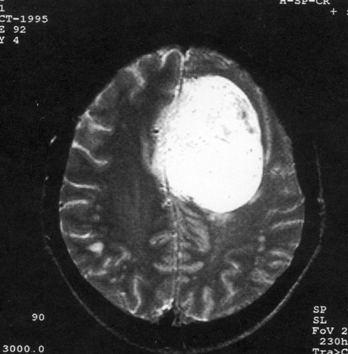

问题 病历摘要:??患者女性,37岁。大便时突起炸裂样头痛3小时,伴喷射样呕吐。既往体健。体检:T37.5℃,BP145/90mmHg,R20次/分,P85次/分。神志清楚,颅神经检查无异常,颈强直,克、布氏征(-),四肢肌力、肌张力正常,病理征(-)。 应首先采取哪些处理措施?提示:CT示右额叶直回处小血肿、蛛网膜下腔出血。